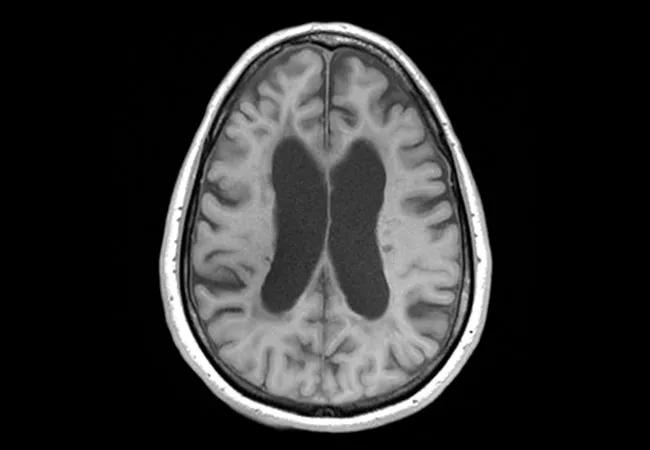

An investigational therapy for progressive forms of multiple sclerosis (MS) with a novel mechanism of action slowed progression of brain atrophy by nearly half relative to placebo over two years of follow-up. So reported investigators with SPRINT-MS, a multicenter phase 2 study presented as a late-breaking trial at the 7th Joint ECTRIMS-ACTRIMS Meeting in Paris Oct. 28, 2017. [Editor’s note: The study was published in full in the Aug. 30, 2018, issue of the New England Journal of Medicine.]

One primary end point was change in brain atrophy — which is associated with physical and cognitive disability in MS — as measured by the MRI analysis technique known as brain parenchymal fraction. The other primary end point was safety and tolerability.

On the primary efficacy end point, ibudilast showed a 48 percent relative reduction in brain atrophy rate versus placebo (P = .04). On the secondary end point of MTR, ibudilast was associated with a 77 to 82 percent reduction in rate of decline versus placebo, with superior outcomes for normal-appearing overall brain tissue as well as gray matter. In contrast, there was no significant difference from placebo in DTI findings.